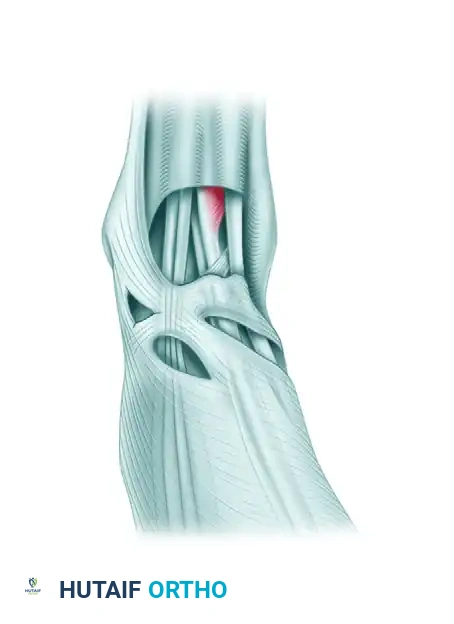

- Beneath the Inferior Extensor Retinaculum: The second common site of rupture is beneath the superomedial limb of the inferior extensor retinaculum. As this limb of the retinaculum reaches the anterior tibial tendon from its lateral side, it divides into an anterior and posterior "glove," completely encircling the tendon as it passes toward its insertion on the medial midfoot.

Figure 82-41: Numbers 3 and 4 point to the superior and inferior subdivisions of the superomedial band of the inferior extensor retinaculum. This split envelops the tendon. 1, Stem of inferior extensor retinaculum; 2, anterior tibial tendon; 5, inferior limb of inferior extensor retinaculum.

Clinical Pearl: Synovitis around the ankle joint can severely constrict the ATT within this retinacular envelope. The resulting extrinsic pressure induces localized ischemic changes within the tendon's watershed zone, precipitating attritional rupture.

Any surgical scar across the anteromedial aspect of the ankle has a high propensity to hypertrophy due to the lack of subcutaneous fat and constant friction from footwear. Meticulous tissue handling and precise incision placement are critical. If tenosynovectomy is required, the surgical approach must be designed so that the sheath of the anterior tibial tendon is accessed while preserving one or both limbs of the inferior extensor retinaculum to prevent postoperative tendon bowstringing.

Step 5: Retinacular Management

* If severe constriction is present, incise the superomedial band of the inferior anterior retinaculum.

* Surgical Pearl: Resuturing this specific band is generally unnecessary, technically difficult, and may recreate the ischemic constriction that led to the pathology.